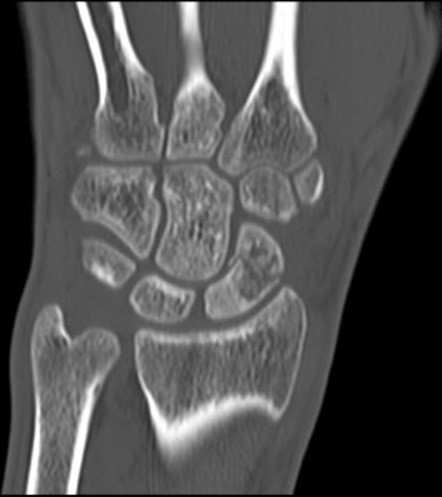

Na obrazie TK nadgarstka uwidocznione jest złamanie kości

A. główkowatej.

B. łódeczkowatej.

C. haczykowatej.

D. księżycowatej.